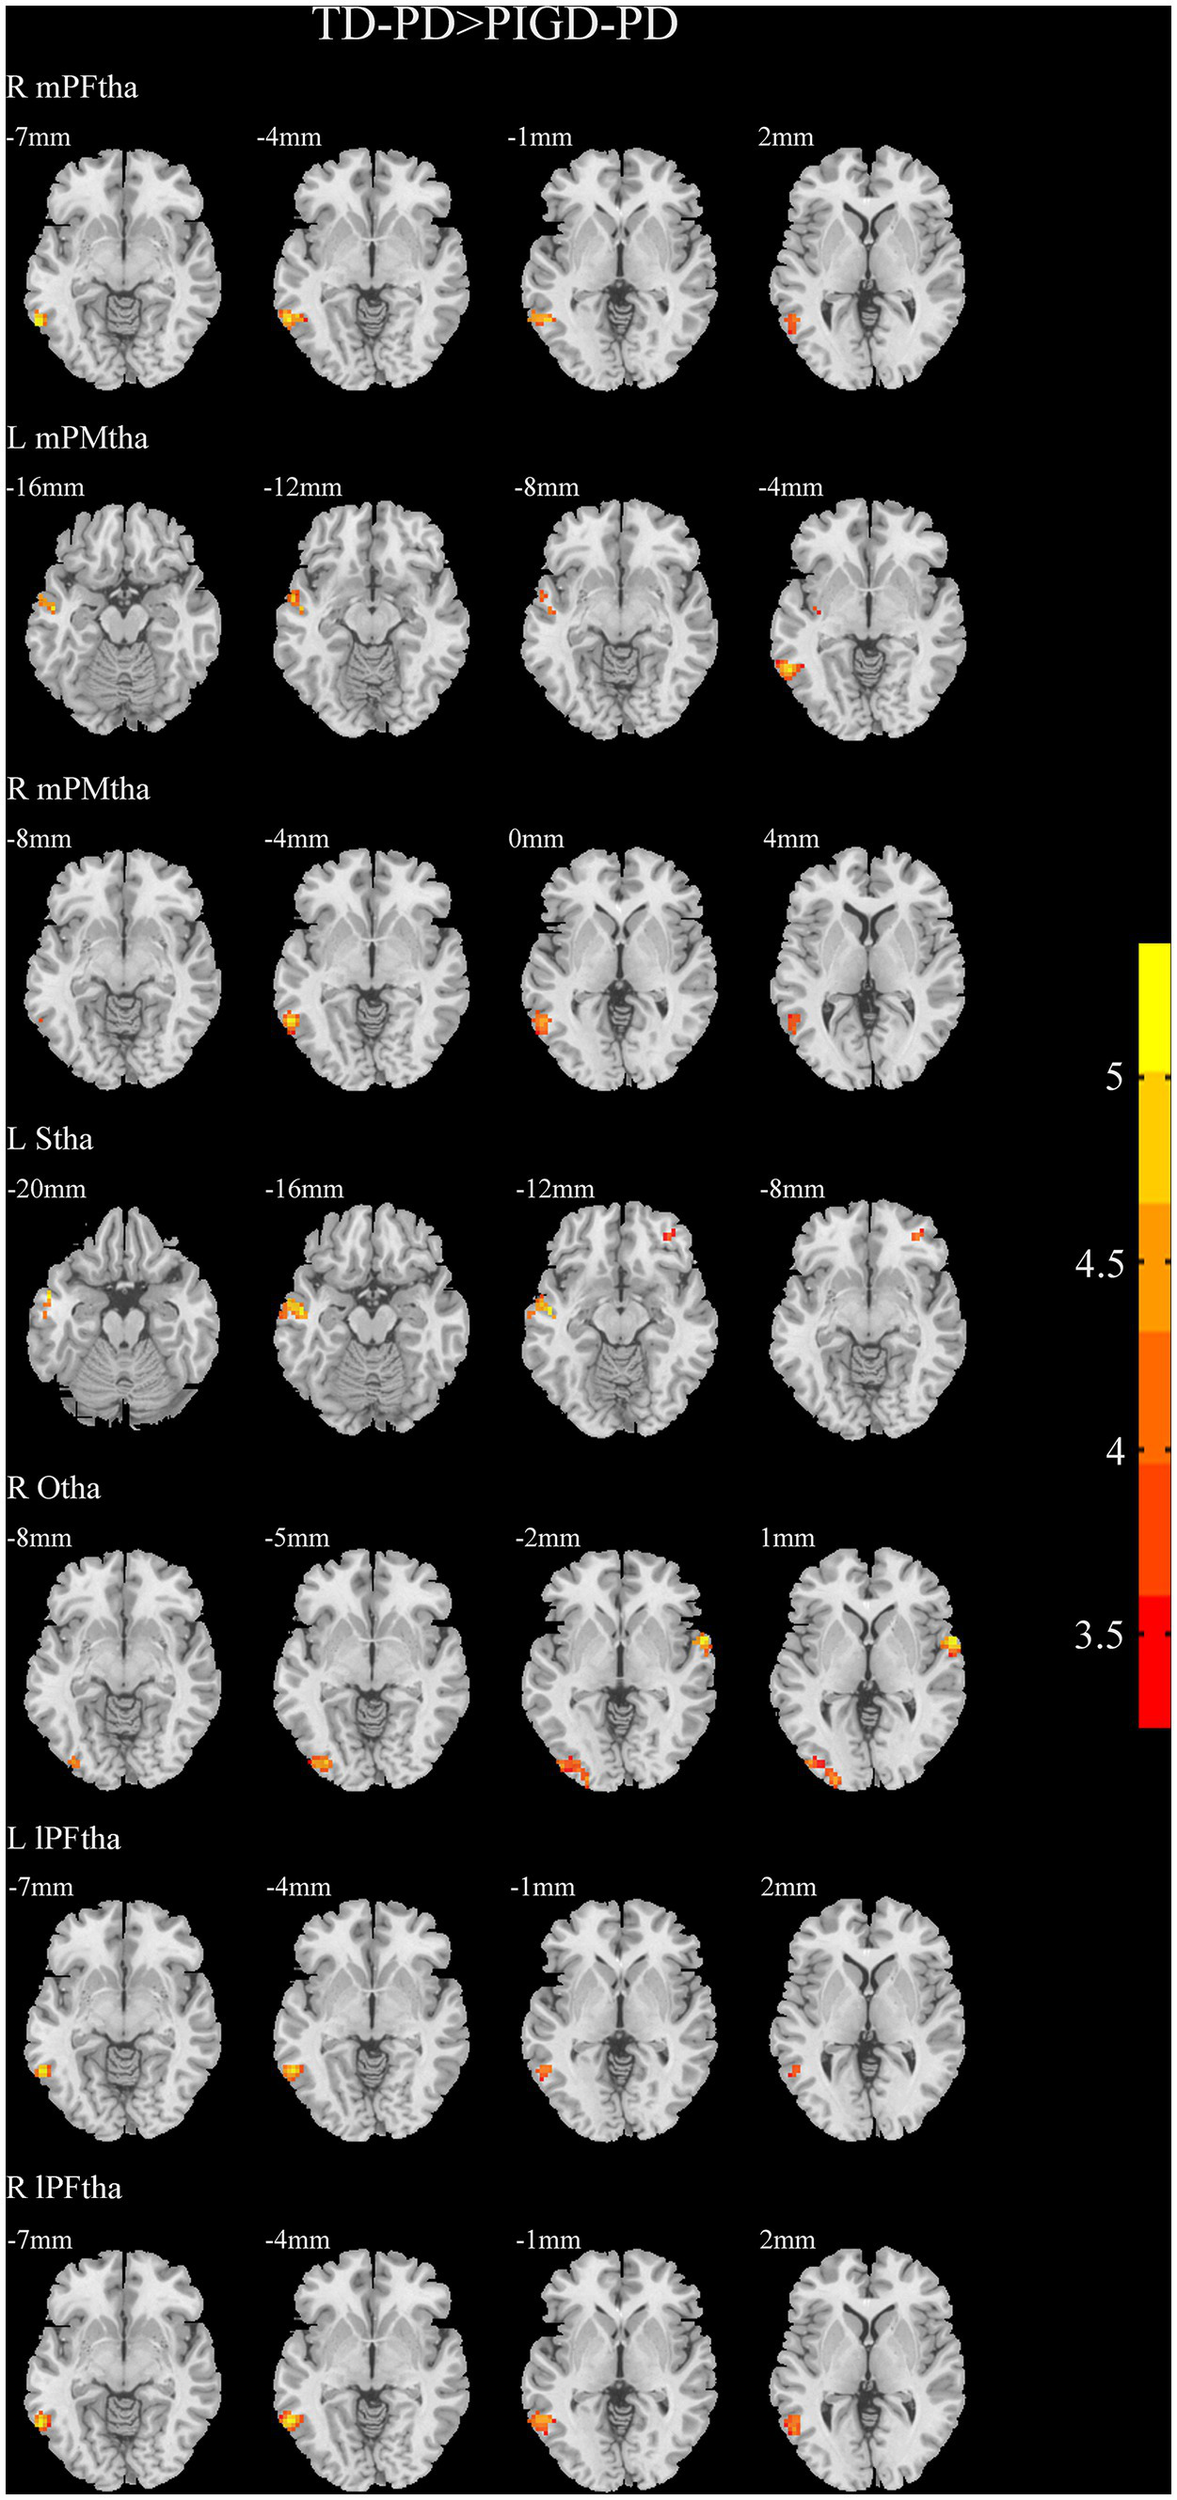

A two-sample t-test of the differences between the TD and PIGD patients showed that the TD group had higher FC between the right mPFtha, bilateral mPMtha, left Stha, bilateral lPFtha, and the left MTG; between the left Stha and the right SFGdl; and between the right Otha and the left MOG, as well as the right STG (Figure 3). The FC between left Stha and the right SFGdl and between the right Otha and the left MOG in the TD group was higher than that in the HC group (Figure 4). The PIGD group had lower FC between the left MTG and the left mPMtha, as well as bilateral lPFtha than the HC group (Figure 5).

Figure 3

Results of two-sample t-test between TD patients and PIGD patients. All results are in MNI space, the red color represents the increased FC, while the blue color represents the decreased FC (voxelwise threshold of p < 0.001 combined with a GRF-corrected clusterwise threshold of p < 0.05).